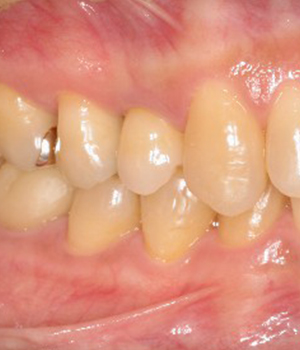

下顎の症例 支台歯はメタルアバットメント

- 術前

- 術中

- 術後

治療期間 半年 費用 100万(税別)

右下はインプラントを2本埋入しました

噛む力が強いのでメタルアバットメントにしてます

左下はブリッジで対応してます

術後8年 現在メインテナンス中で経過良好です

リスク・副作用としてインプラント周囲炎があります